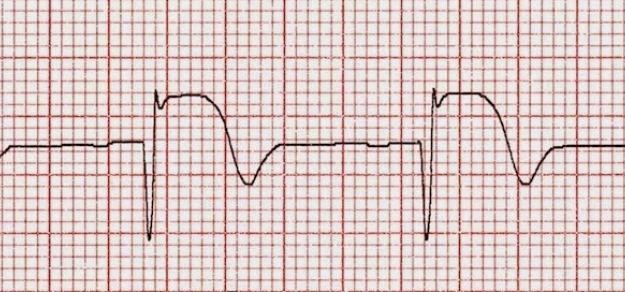

Se ha actualizado la guía norteamericana sobre las medidas iniciales frente al accidente cerebrovascular isquémico, de modo de optimizar las posibilidades tempranas de reperfusión y la protección del área de penumbra. Stroke, 24 de enero de 2018